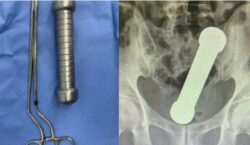

Mengadu tak dapat buang air besar, doktor jumpa dumbbell dalam dubur